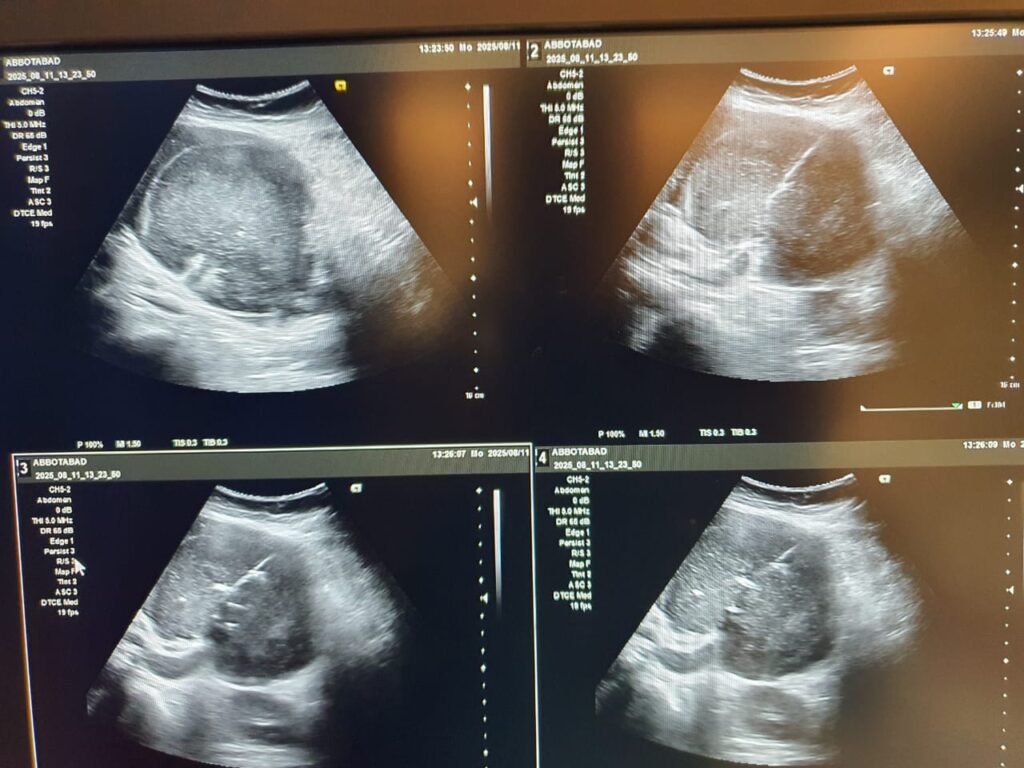

Gall Bladder Fossa Abscess Drain Placement

Founded by Dr. Atif Nawaz and Dr. Muhammad Ismail Alvi, our Interventional Radiology Unit at NIRS Pakistan is dedicated to delivering safe, effective, and patient-centered care for managing complex abdominal infections. Using state-of-the-art imaging and minimally invasive techniques, we provide Gall Bladder Fossa Abscess Drain Placement — a procedure that involves precise, image-guided catheter drainage to remove pus and infection without the need for open surgery.

A gall bladder fossa abscess is a localized collection of pus that may develop after gall bladder surgery, trauma, or infection. If left untreated, it can cause severe pain, fever, and systemic infection. Image-guided abscess drain placement is a safe and effective procedure to remove the infection without the need for open surgery.

At NIRS Pakistan, our Interventional Radiology team performs minimally invasive, image-guided abscess drainage with precision. This approach avoids major surgery, shortens hospital stays, reduces complications, and promotes faster recovery for patients.